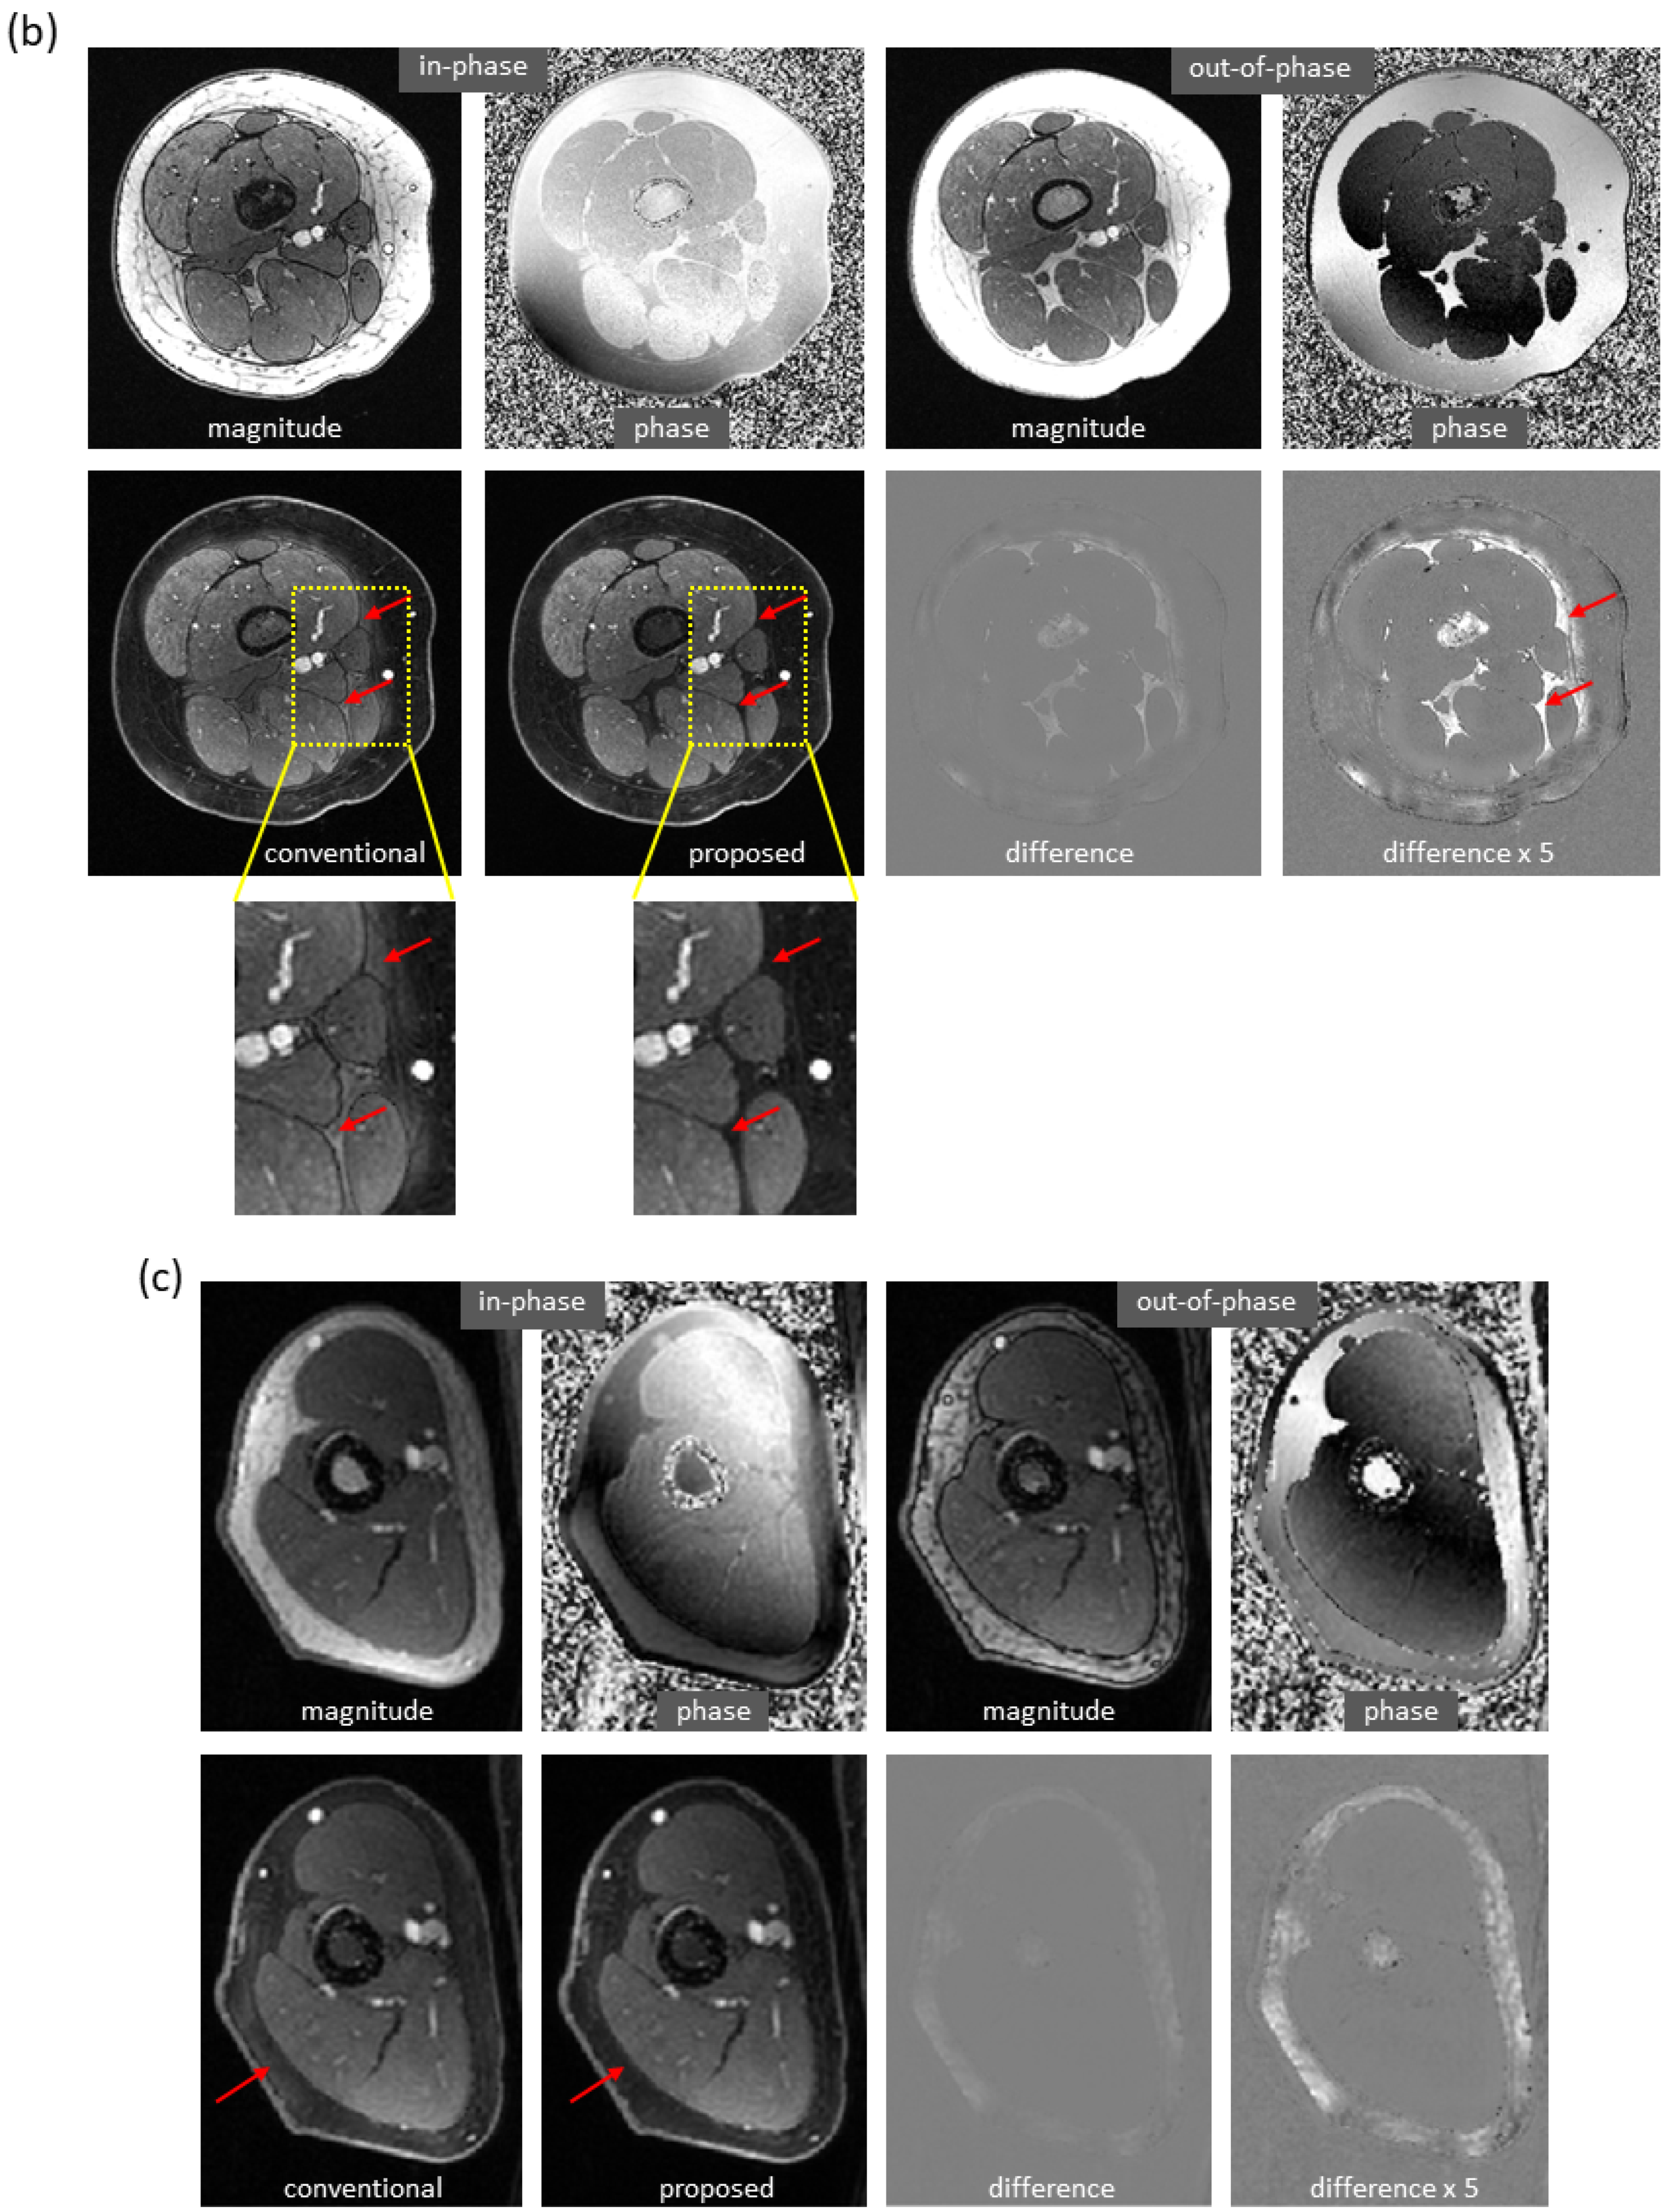

Using the proposed method, water/fat swaps that appeared in reference images were mitigated in the predicted images. Figure 4 demonstrates some examples with minor water/fat swaps. In Figure 4a, inhomogeneities (in a slice far away from the isocenter) led to artifacts in a reference image of the knee; the artifacts did not appear in the predicted image. Here, tumor and adjacent nerve were well delineated in the predicted image, which is critical for surgical planning. In Figure 4b,c, a more complete separation of water and fat signals was achieved in the predicted images of the knee and arm. In Figure 4d, local water/fat swaps in a reference image of the foot were largely compensated in the predicted image. Notably, these images of the arm and foot were inferred using models trained with only knee data, and the robustness of the proposed approach to out-of-distribution data was demonstrated.

Figure 4.

Mitigation of slight water/fat swaps. (a) Artifacts in an off-isocenter reference image of the knee (blue arrows), which were introduced by severe inhomogeneities, were automatically compensated in the predicted image. Here, tumor (red arrows) and adjacent nerve (green arrows) were well separated in the predicted image. (b) Water–fat separation was improved in the predicted image of the knee as compared to the reference image, which had regions of error (arrows). (c) More complete water–fat separation was observed in the predicted image of the arm, even if the deep learning model was trained with only knee images. (d) Some local water/fat swaps that appeared in the reference image of the foot did not occur in the predicted image. It is of note that the images (c,d) demonstrated the robustness of the approach to out-of-distribution data.